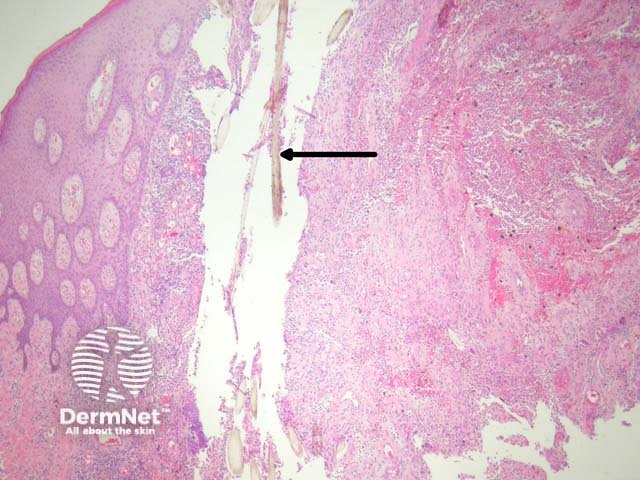

Sections show a dense inflammatory reaction usually occupying the entire dermis with erosion and ulceration of the overlying epidermis (figure 1). Free hair shafts are often seen coursing through the inflammatory focus (figure 2, arrow). Often, the free hair shafts are seen in clusters (figure 3). Dye used to outline the sinus tract for the surgeon may sometimes be seen. Surrounding the free hair shafts is a polymorphous infiltrate which may be rich in plasma cells and lymphocytes (figure 4). Foreign body-type giant cells and neutrophilic abscesses are also commonly observed.

Figure 1